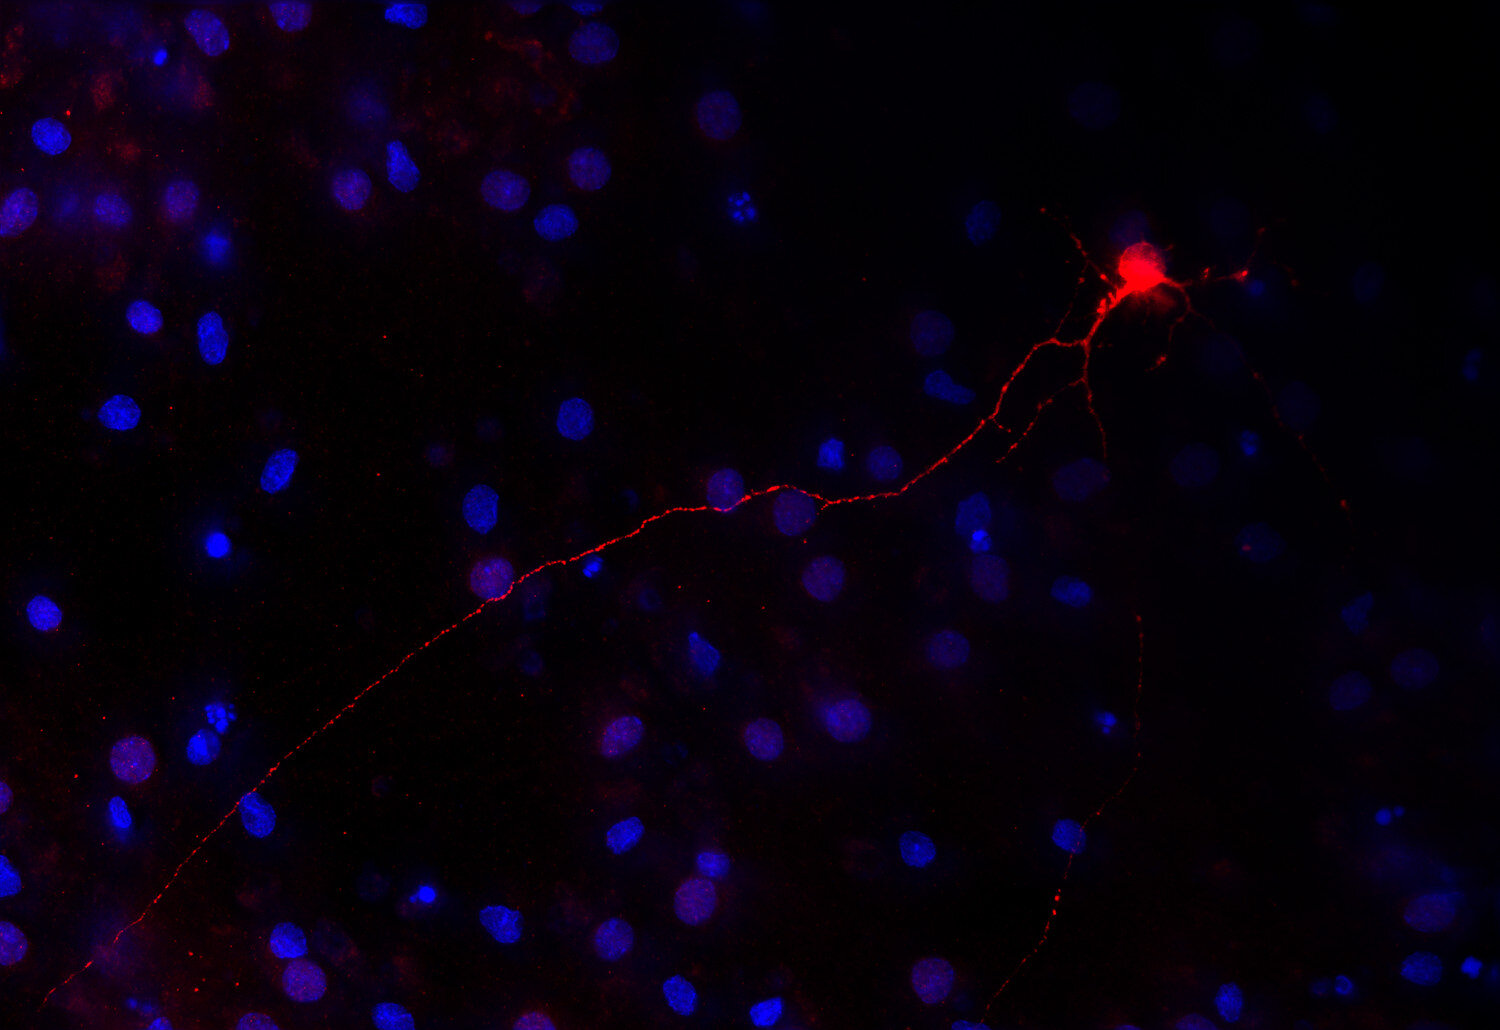

IHC: 1 : 1000 up to 1 : 10000 (see remarks) gallery

Immunohistochemistry (IHC) on 4% PFA perfusion fixed tissue with 24h PFA post fixation. Immunoreactivity is usually revealed by fluorescence or a chromogenic substrate. Some antibodies require special fixation methods or antigen retrieval steps. For details, please refer to the ”Remarks” section.

Cell reports (2023) 423: 112231. 213 211 IHC; tested species: mouse

Tyrosine hydroxylase is one of the key enzymes in the synthesis pathway of catecholamines like adrenalin, noradrenalin and dopamin and is frequently used as a marker for dopaminergic neurons. This neuronal subpopulation is especially affected in Parkinson's disease.